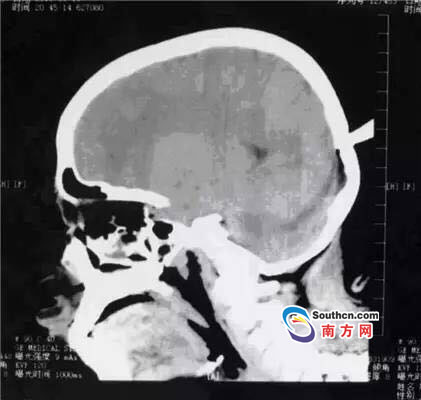

接到小玲受傷的消息,東莞市第三人民醫(yī)院急診科立即啟動了急癥危重患者搶救流程。急癥頭部CT顯示,飛鏢已穿透小玲的顱骨,并突破硬腦膜,情況非常兇險,小玲命懸一線。

此時,小玲也處于極度恐懼和不安中。醫(yī)生表示,必須及時手術(shù)取出異物、止血并妥善處理顱內(nèi)相關(guān)損傷,否則飛鏢將進一步損傷腦組織,引起二次傷害,甚至可能引發(fā)顱內(nèi)大出血。搶救刻不容緩,醫(yī)院神經(jīng)外科醫(yī)師立即與麻醉手術(shù)科聯(lián)系,開通綠色通道準備急診手術(shù)。

開顱還是不開顱?這是擺在神經(jīng)外科醫(yī)生面前最重要的問題。此時的檢查結(jié)果無法判斷有無血管和腦組織的損傷,開顱手術(shù)可以直接看到損傷的情況,及時進行處理,但是如果飛鏢沒有損傷大血管,開顱的話就會造成比較大的創(chuàng)傷;不開顱手術(shù),手術(shù)的全過程造成的損傷就會減少,但是如果有大血管的損傷,不開顱直接拔出飛鏢,就不能及時進行止血和清創(chuàng)。

兩種選擇都是機會與風(fēng)險并存的,最后神經(jīng)外科通過會診,在充分征求家屬意見的基礎(chǔ)上,決定進行不開顱手術(shù),同時,也充分考慮手術(shù)風(fēng)險,做好開顱手術(shù)的一切準備。